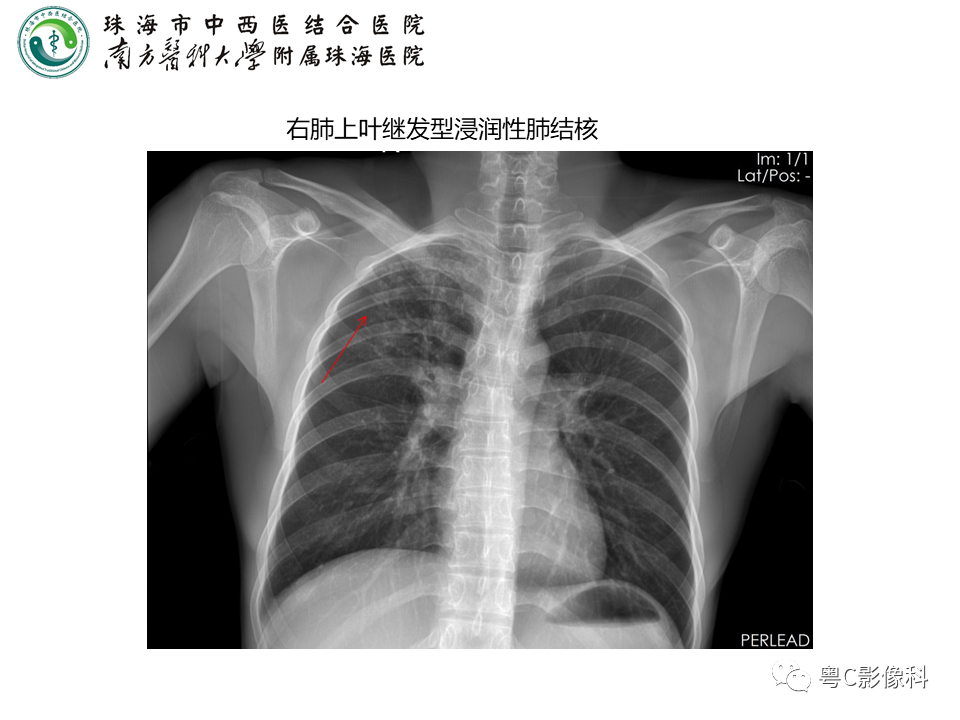

胸部平片解读!